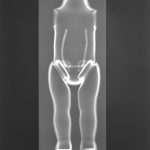

Distanced from the actual procedures (at the time) I was able to study these images for what they were. The half-familiar and recognizable bony structures, barium meal enemas, brain and body scans which became mingled with my X-rays of exotic flowers, fruit and vegetables (dipped in barium meal) plus dolls limbs and heads.

The barium meal study of the colon and the orchid became of equal interest, stripped of their vivid colour, they have the same translucency and ethereal quality.

Similarities were seen between a pepper and a text book heart, a bundle of parsley and cerebral blood vessels. Dislocated dolls heads and limbs became floating body parts.